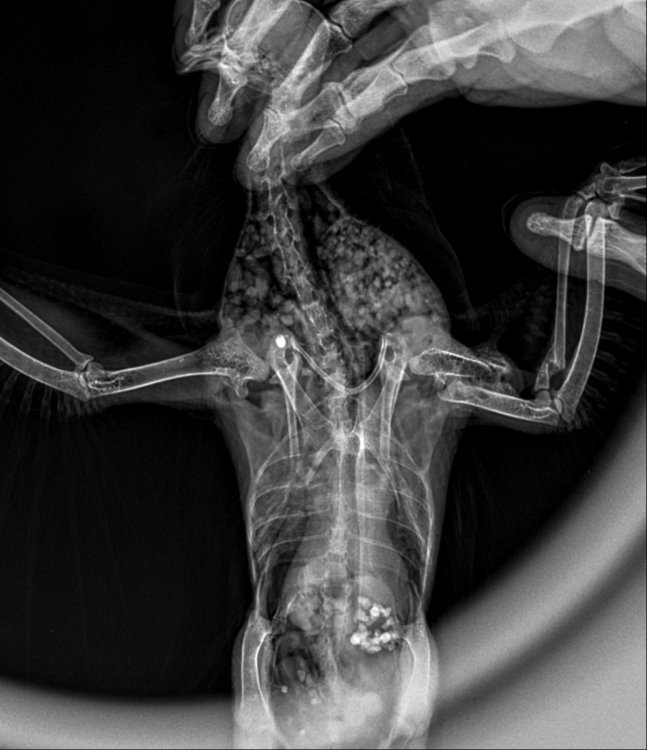

Серая ворона Геша, 12 лет. Был подобран маленьким птенцом. Никогда не болел. Живет в вольере на улице. Выкармливали и растили благодаря форуму по врановым на mybirds. Сейчас заканчивает линьку. Позавчера утром обнаружили его лежащим на животе с распластанными крыльями. Стоять не может. Лапки висят и не реагируют ни на что. Аппетит плохой, съел только немного промороженных насекомых. Были в клинике. Сделали рентген. Получили заключение и рекомендации, но мучают сомнения:( Птице очень плохо. Может специалисты посмотрят наши снимки🙏

E104C390-EF90-44CD-BF48-0376CF3E676C.jpeg

03F9A086-38BB-4609-9283-E09C83A7C715.jpeg

C3D20BF0-AF12-43C6-9388-E6DCDD44A749.jpeg

6572F185-2473-4DD0-8AC5-725CE4A319CE.jpeg

Нижний снимок голубя. Для срочного ответа пишите Zosia по Вацапу.